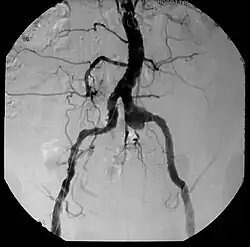

El diagnóstico debe basarse en la sospecha clínica apoyada en las técnicas de imagen, como la angiografía y la tomografía computarizada (TC), técnica de elección para la detección del aneurisma. La TC es decisiva en el diagnóstico de los aneurismas micóticos. Una vez detectados deben tratarse sin demora, pues su evolución natural es hacia la rápida expansión y rotura. La angiografía ayuda a planificar el tratamiento. La radiología intervencionista representa un papel importante en el tratamiento.[4]